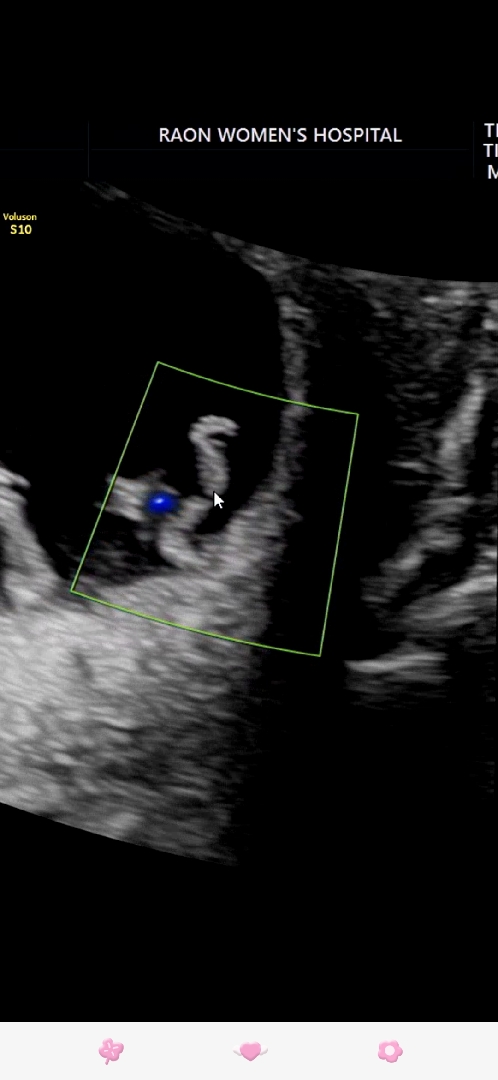

10주 2일 발바닥 인가요? (초음파사진)

이거 발바닥일까요?

발가락이 다섯개 잘보이네용 ㅎㅎ

발바닥 넘 귀여우ㅏ요 ㅎㅎㅎㅎ